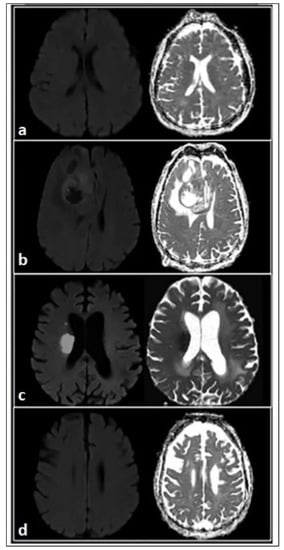

- Moritani, T.; Shrier, D.A.; Numaguchi, Y.; Takahashi, C.; Yano, T.; Nakai, K.; Zhong, J.; Wang, H.Z.; Shibata, D.K.; Naselli, S.M. Diffusion-Weighted Echo-Planar MR Imaging of CNS Involvement in Systemic Lupus Erythematosus. Acad. Radiol. 2001, 8, 741–753. [Google Scholar] [CrossRef]

- Welsh, R.C.; Rahbar, H.; Foerster, B.; Thurnher, M.; Sundgren, P.C. Brain Diffusivity in Patients with Neuropsychiatric Systemic Lupus Erythematosus with New Acute Neurological Symptoms. J. Magn. Reson. Imaging 2007, 26, 541–551. [Google Scholar] [CrossRef]

- Valdez-López, M.; Aguirre-Aguilar, E.; Valdés-Ferrer, S.I.; Martínez-Carrillo, F.M.; Arauz, A.; Barrera-Vargas, A.; Merayo-Chalico, J. Posterior Reversible Encephalopathy Syndrome: A Neuropsychiatric Manifestation of Systemic Lupus Erythematosus. Autoimmun. Rev. 2021, 20, 102739. [Google Scholar] [CrossRef]

| Bosma et al., 2003 [52] | 11 NPSLE (past NP involvement), 10 HCs. | DWI | NPSLE vs. HCs: lower peak height and higher mean ADC values (whole brain). |

| Bosma et al., 2004 [53] | 24 NPSLE (past NP involvement). | DWI, MTI, MRS | Correlation between reduced MTRp and increased mean ADC values (whole brain). |

| Emmer et al., 2006 [54] | 37 NPSLE (past NP involvement), 21 SLE, 12 HCs. | DWI | Lower mean ADC values at amygdala level in SLE and NPSLE compared to HCs, in particular for NMDAR-Ab positive patients. |

| Welsh et al., 2007 [49] | 17 acute NPSLE (within one week from symptoms onset), 21 HCs. | DWI | Higher ADC values at whole brain, GM and WM levels for acute NPSLE compared with HCs. |

| Hughes et al., 2007 [55] | 8 acute NPSLE (within one week from symptoms onset), 20 HCs. | DWI, DTI | NPSLE vs. HCs: increased ADC values and decreased FA at thalamus, parietal and frontal WM levels. |